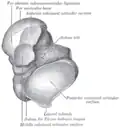

Talus - inferior view -

Lateral view of the human ankle, including the talus